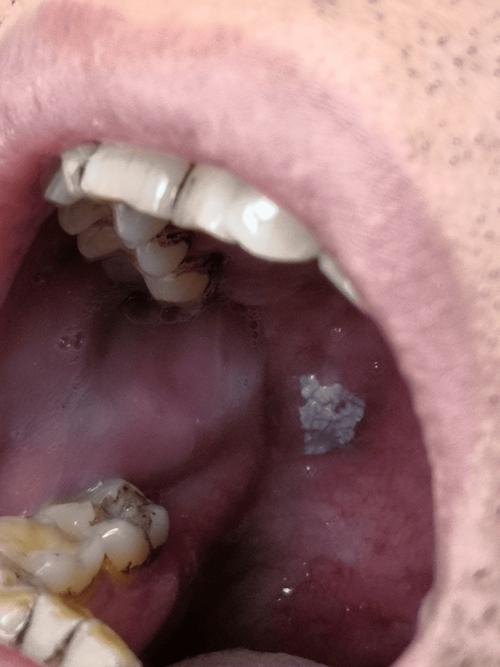

扁平苔藓 (Lichen Planus)

一种原因不明的慢性炎症性皮肤黏膜病。

- 外观:

- 典型表现为“网状”或“花纹状”的白色条纹(称为Wickham纹),可以呈灰色或蓝色。

- 这些条纹可以相互交叉,形成网状图案,常见于颊黏膜、舌、牙龈等处。

- 有时也会出现白色丘疹或斑块。

- 伴随症状:

- 大多数患者没有明显症状,但部分人可能感到口腔粗糙、灼痛,尤其在吃辛辣、酸性食物时加重。

- 有少数病例(约1%-5%)有癌变风险,需要定期复查。

- 处理:病因不明,无法根治,但可以控制症状,需就医,医生可能会开具糖皮质激素类药物(如含片、凝胶)来缓解炎症和疼痛,并建议定期随访。